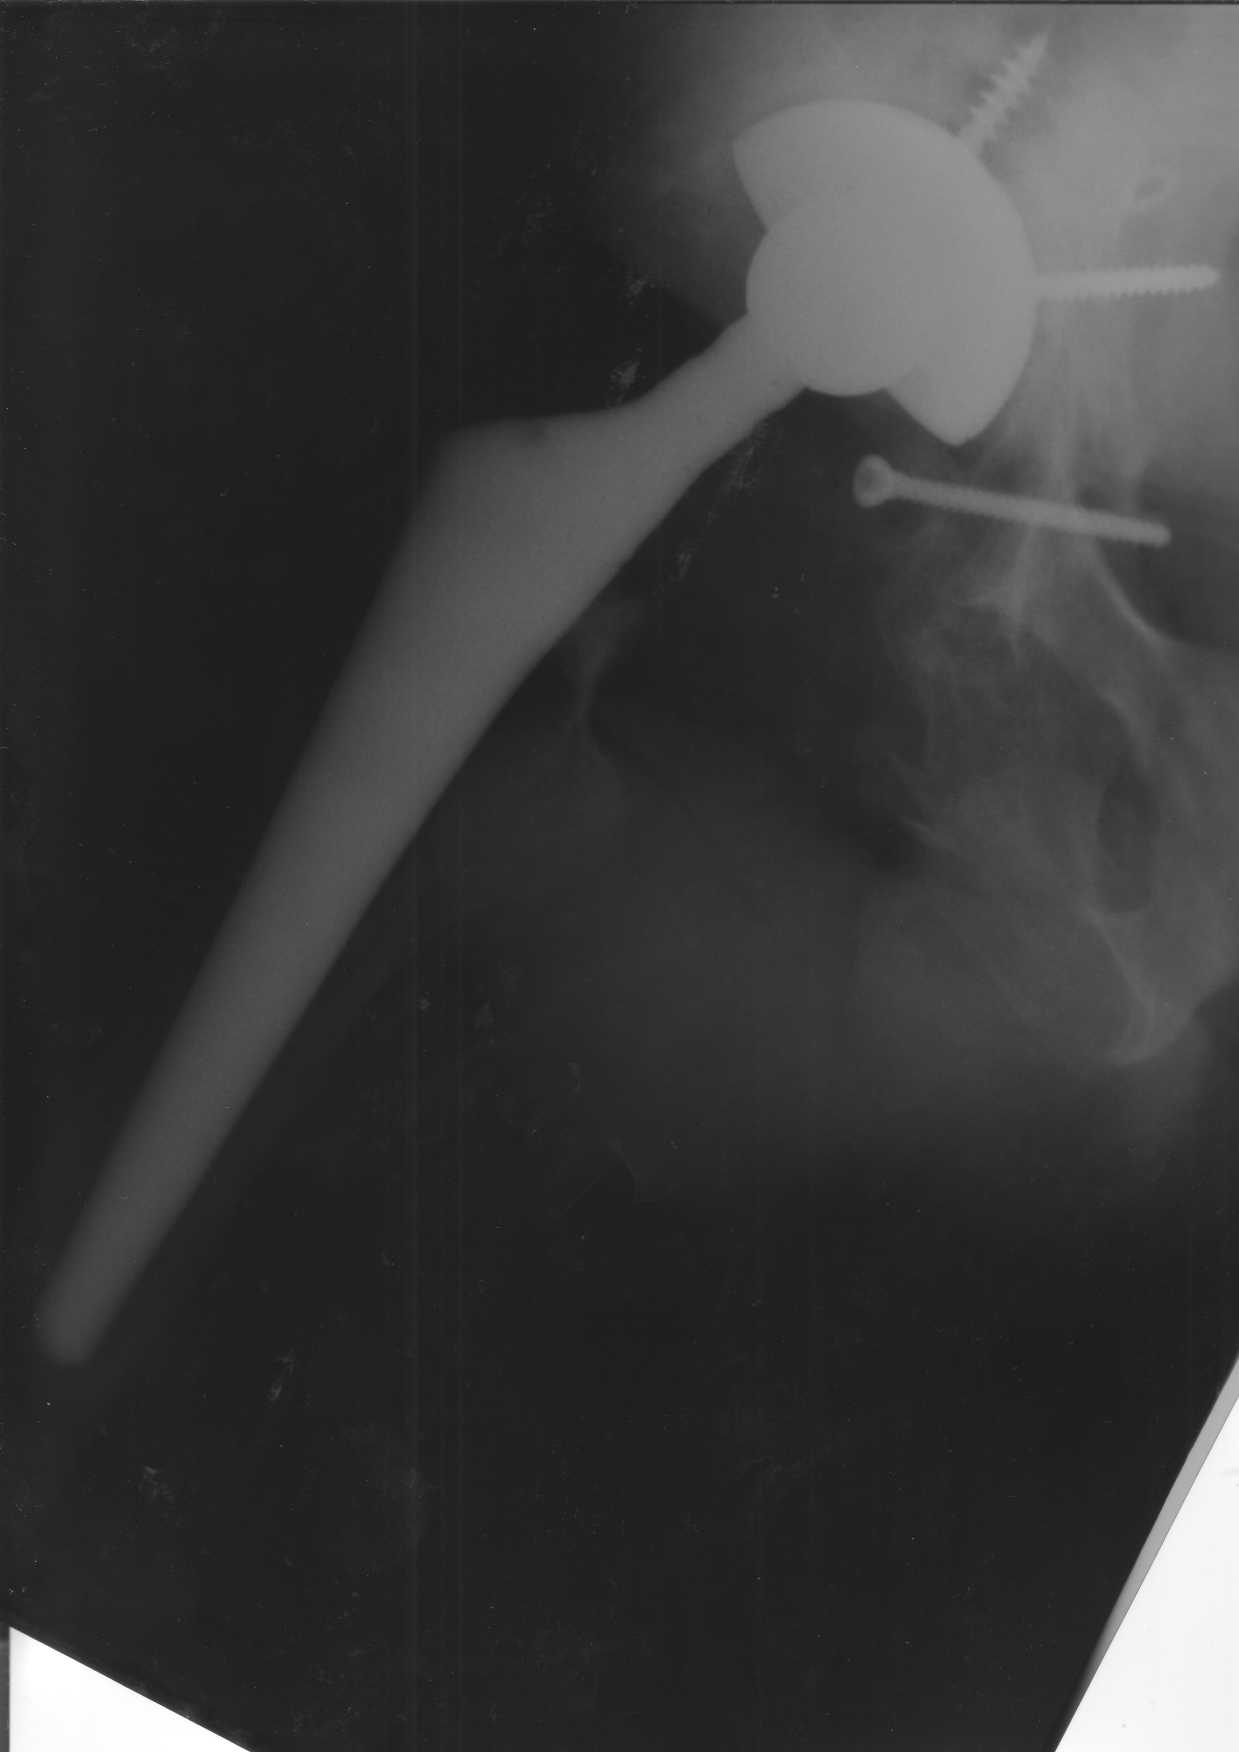

Уважаемые коллеги.В 3 Центральный Военный Клинический Госпиталь имени А. А. Вишневского, что в Красногорске, Московской области, в отделение эндопротезирования крупных суставов поступил пациент 1960 года рождения Жалобы при поступлении: на боли в области левого тазобедренного сустава (больной указывает на точку расположенная в середине условной линии между седалищным бугром и большим вертелом), усиливающиеся в начале ходьбы, при опоре на левую ногу с иррадиацией болей по наружной и наружно-задней поверхности левого бедра, левый коленный сустав; снижение объема движения в левом тазобедренном суставе, снижение опорной способности левой нижней конечности, хромоту на левую ногу, необходимость использования дополнительной опоры (костыли) при ходьбе, снижение объема двигательной активности из за болей в суставе.В анамнезе: Со слов больного, согласно медицинских документов, в 1989 году получил травму левой нижней конечности: закрытый перелом левой вертлужной впадины с центральным вывихом головки левой бедренной кости. Лечился консервативное. В процессе лечения сформировался посттравматический артроз, укорочение левой нижней конечности до 5 см. 25.04.2005 года в Подольском Окружном Госпитале Министерства Обороны выполнено: одномоменто, остеосинтез заднего края вертлужной впадины фрагментом резецированной головки бедренной кости и тотальное эндопротезирование левого тазобедренного сустава бесцементным эндопротезом "VERSIS ET" с бесцементной чашкой TRILOGY. Послеоперационный период осложнился ранним нагноением области эндопротеза, в результате санаций очага инфекции и антибиотикотерапии, активного промывного дренирования антисептиками, послеоперационная рана зажила. После операции, со слов больного, через два месяца в полном объеме стал нагружать левую нижнюю конечность. В течение полгода, после операции чувствовал себя вполне удовлетворительно. С марта 2006года стал отмечать появление болей в области тазобедренного сустава, то в области паха, то в области левой ягодицы. С августа месяца отмечает те жалобы, с которыми он сейчас к нам обратился. Температура тела, после заживления раны, нормальная. В анализах крови, лейкоциты около 7 тыс, формула нормальная, СОЭ 12 мм ч. Локально: при осмотре обеих нижних конечностей, анатомическая ось конечности не нарушена; отмечено относительное укорочение левой н\конечности на 1.5 см., гипотрофия мышц левого бедра 3 см, голени 2 см, симптом. Объем движений в тазобедренных суставах: правый~ сгибание- 60 гр, разгибание-180 гр ,отведение- 35 гр, левый~ сгибание- 110 гр , разгибание-170 гр , отведение-15 гр. Контуры других суставов н/конечностей обычные, объем движений в них не страдает. Пульсация на артериях конечностей удовлетворительная. Неврологические нарушения конечностей отсутствуют, рефлексы на обеих н/конечностях одинаковые, чувствительных нарушений нет. Осевая нагрузка на левую нижнюю конечность вызывает боль в точке расположенная в середине условной линии между седалищным бугром и большим вертелом. Отмечается пигментация и пастозность нижней трети обеих голеней и стоп, характерная для посттромботической болезни. На Цветном дуплексном сканировании сосудов нижних конечностей: Нестенозирующий атеросклероз обеих бедренных и подколенных артерий . Гемодинамически значимых препятствий кровотоку в магистральных артериях ног не выявлено. Глубокие и поверхностные вены нижних конечностей проходимы. Умеренная недостаточность клапанов подколенных вен. Данных за тромбоз глубоких вен на момент осмотра не получено.А вот что пишет наш рентгенолог: На серии рентгенограмм области левого тазобедренного сустава определяется тотальный бесцементный эндопротез. Вокруг тени чашки эндопротеза определяется ободок остеорезорбции. Кроме того, визуализируется деформированный костный винт фиксирующий консолидированный отломок вертлужной впадины, вплотную прилегающий к тени чашки эндопротеза. Заключение: Рентгеновские признаки нестабильности чашки тотального эндопротеза. Лучевая нагрузка: 6 мЗв. У нас в отделении разошлись мнения: начальник мой утверждает, после сравнения снимков, принесенных больным от августа и октября 2006года и наших рентгенснимков, что у больного нет нестабильности вертлужного компонента, и что надо назначит курс консервативной терапии: препараты кальция, миакальцик, увеличить осевую нагрузку на левую нижнюю конечность, ЛФК направления на укрепление мышц бедра, ягодиц, физиолечение. А я утверждаю, что у больного клиника нестабильности вертлужного компонента, и необходима ревизия вертлужного компонента, не исключено даже наличие инфекции под чашкой эндопротеза (не смотря на отсутствие клинических признаков инфекции). В результате проводимой консервативной терапии, боли у больного усилились. Помогите рассудить нас, мы готовы выслушать ваши мнения по этому поводу. С уважением Батал Шушания.3 ЦВКГ имени А. А. Вишневского

Ув. Коллега.Четких рентгенологических признаков нестабильности вертлужного компонента действительно нет. Здесь, кроме нестабильности, можно искать причину в поясничный отдел позвоночника(Hip-spain синдром - всё-таки 15 лет ходил с укорочением),либо сделать спиральный КТ и посмотреть, нет ли несращения в области старого перлома вертлужной впадины. Зачастую ложные суставы подвздошной, седалищной, а иногда и лонной костей являются причинами несостоятельности эндопротезов.

поясничного отдела позвоночника. Есть зона остеолиза вокруг чашки, но как правило, дополнительный винт держит чашку достаточно хорошо, и даже при наличии микроподвижности, это не сопровождается столь ярким болевым синдромом. Поэтому, я бы сделал следующее: МРТ позвоночника, пункцию ТБС для исключения инфекционного процесса. Ревизию рассматривал бы как крайний вариант, учитывая выполненную костную пластику и отсутствие явных признаков нестабильности.

уважаемый коллега, Антон Вакуленко. Спасибо за четкий, расписанный по пунктам план действий. При поступлении пациента в отделение, я думал точно как вы. Но на следующий день, выполнил многопроеционное рентгенисследование, показал невропатологу, и доложил начальнику отделения о больном.После разбора пришли к следующему, да у больного действительно нестабильность вертлужного компонента, есть зона лизиса в месте костного аутотрансплантата, а в месте фиксаци чашки деротационным винтом четко выраженный контакт чашки с костной тканю. Мы пришли к выводу,что лизис костного аутотрансплантата из за осевой перегрузки на фоне незавершенного ремоделирования (вес больного 130 кг). Потому мы и приняли план вышеуказанного лечения. Провели беседу с больным, больной согласился с нами. Через 3-6 месяцев мы оценим эффективность лечения и доложу. Возможно и придется тогда идти на ревизию с заменой только вертлужного компонента а может и придется удалить весь эндопротез с установкой спейсера.. посмотрим.....